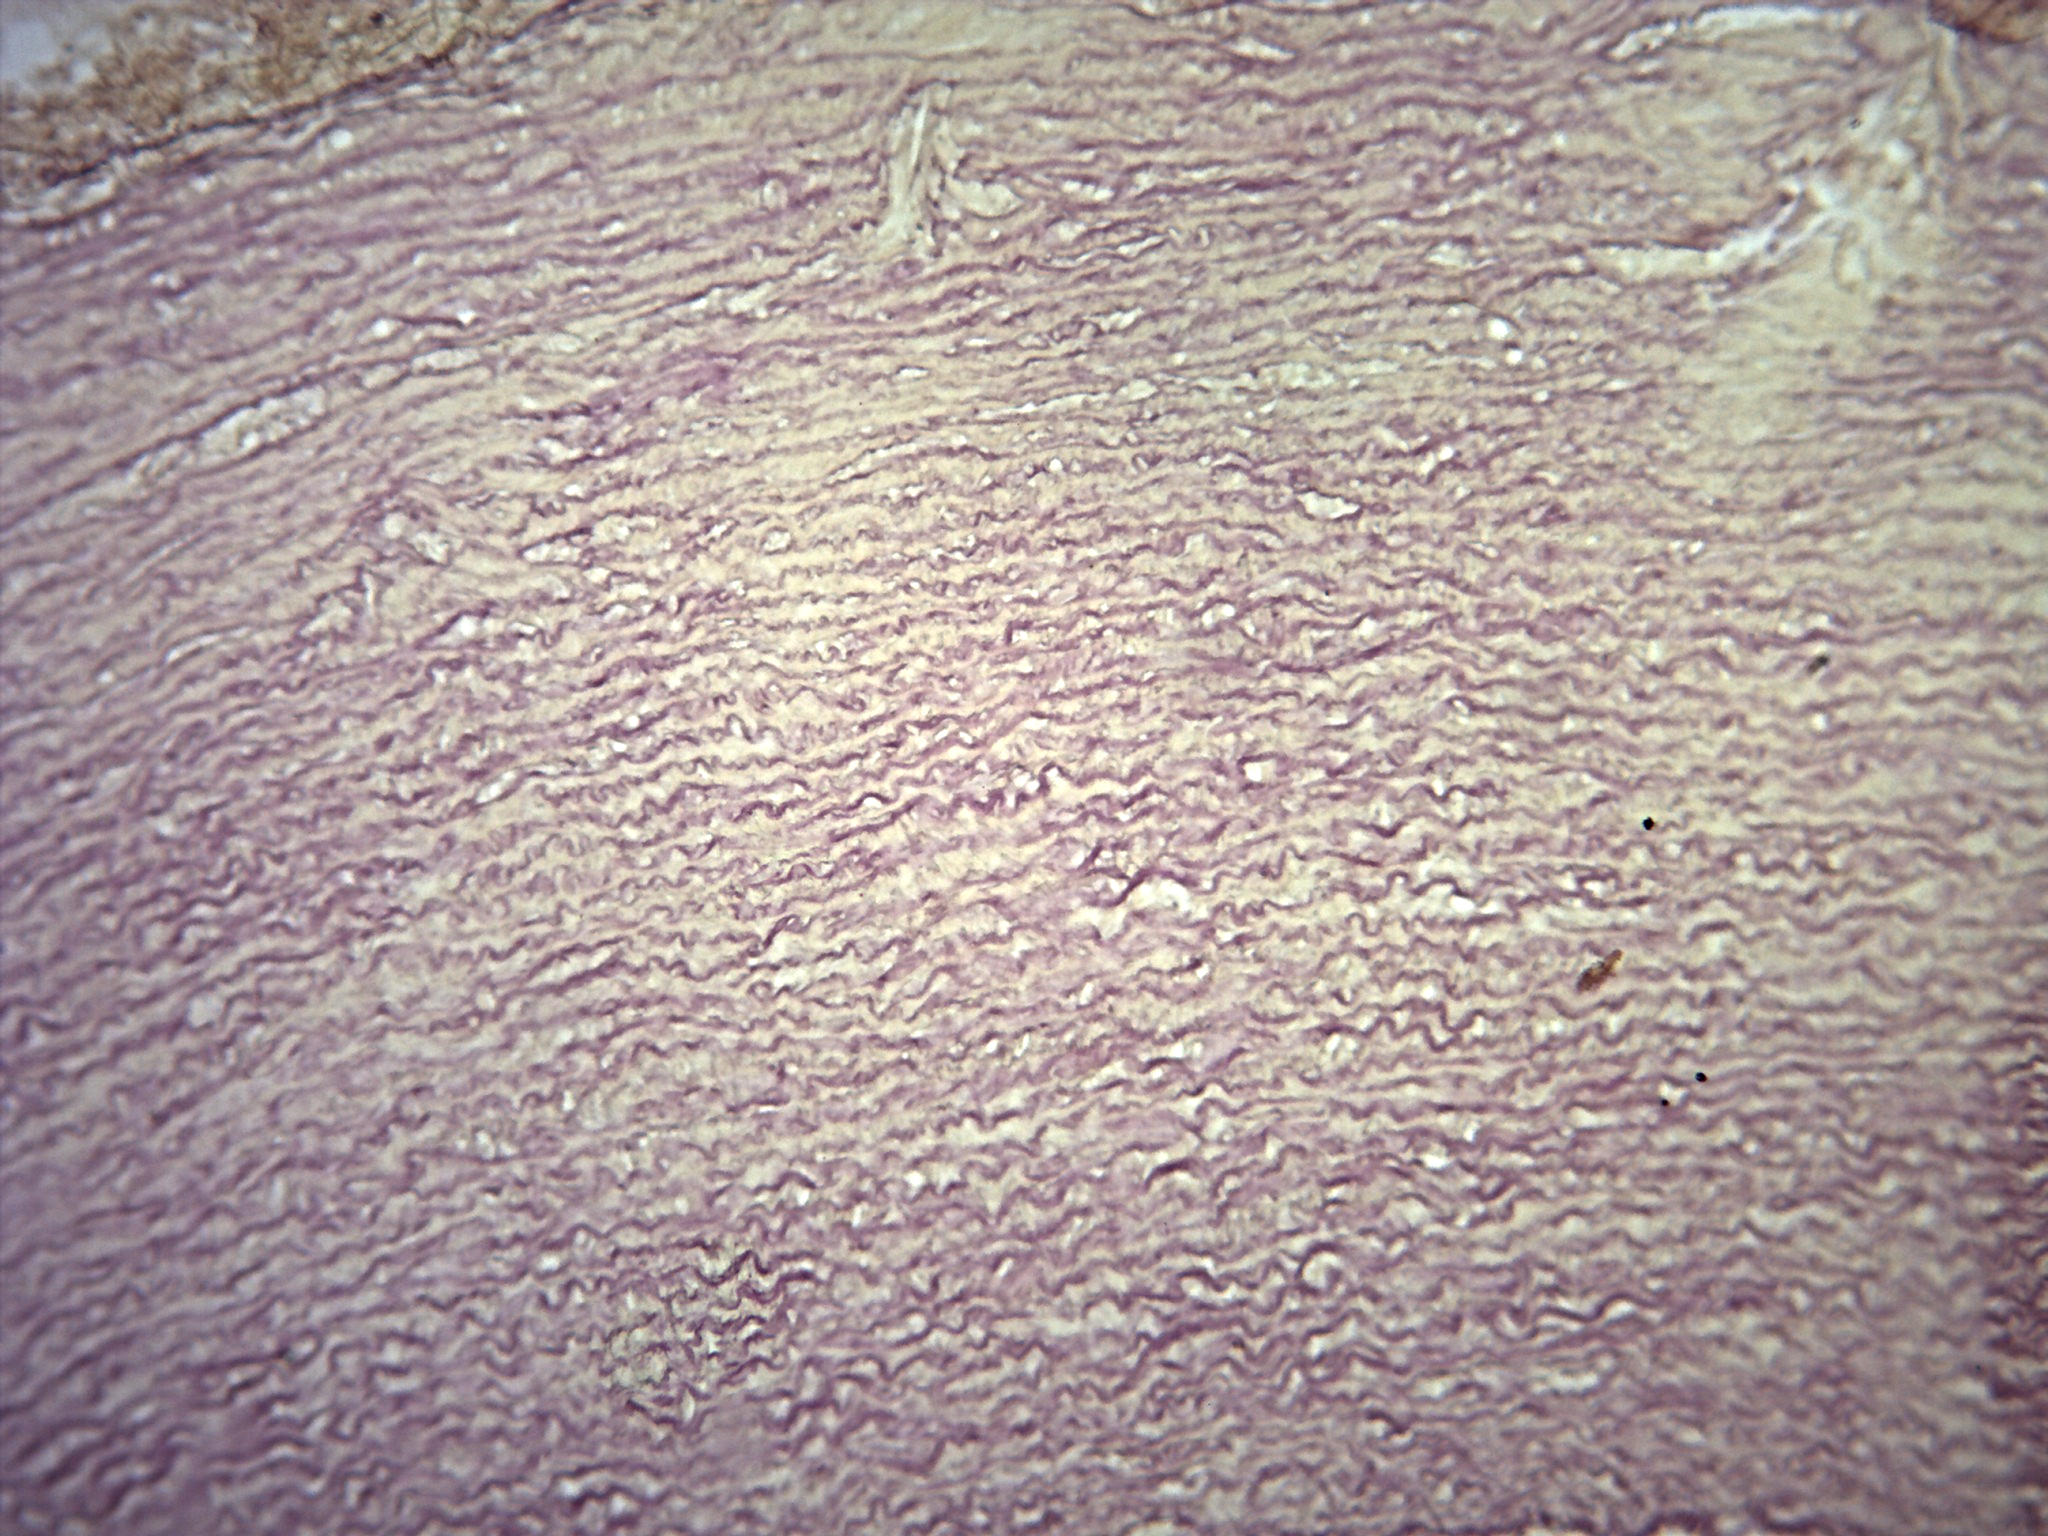

Sistema Circulatório